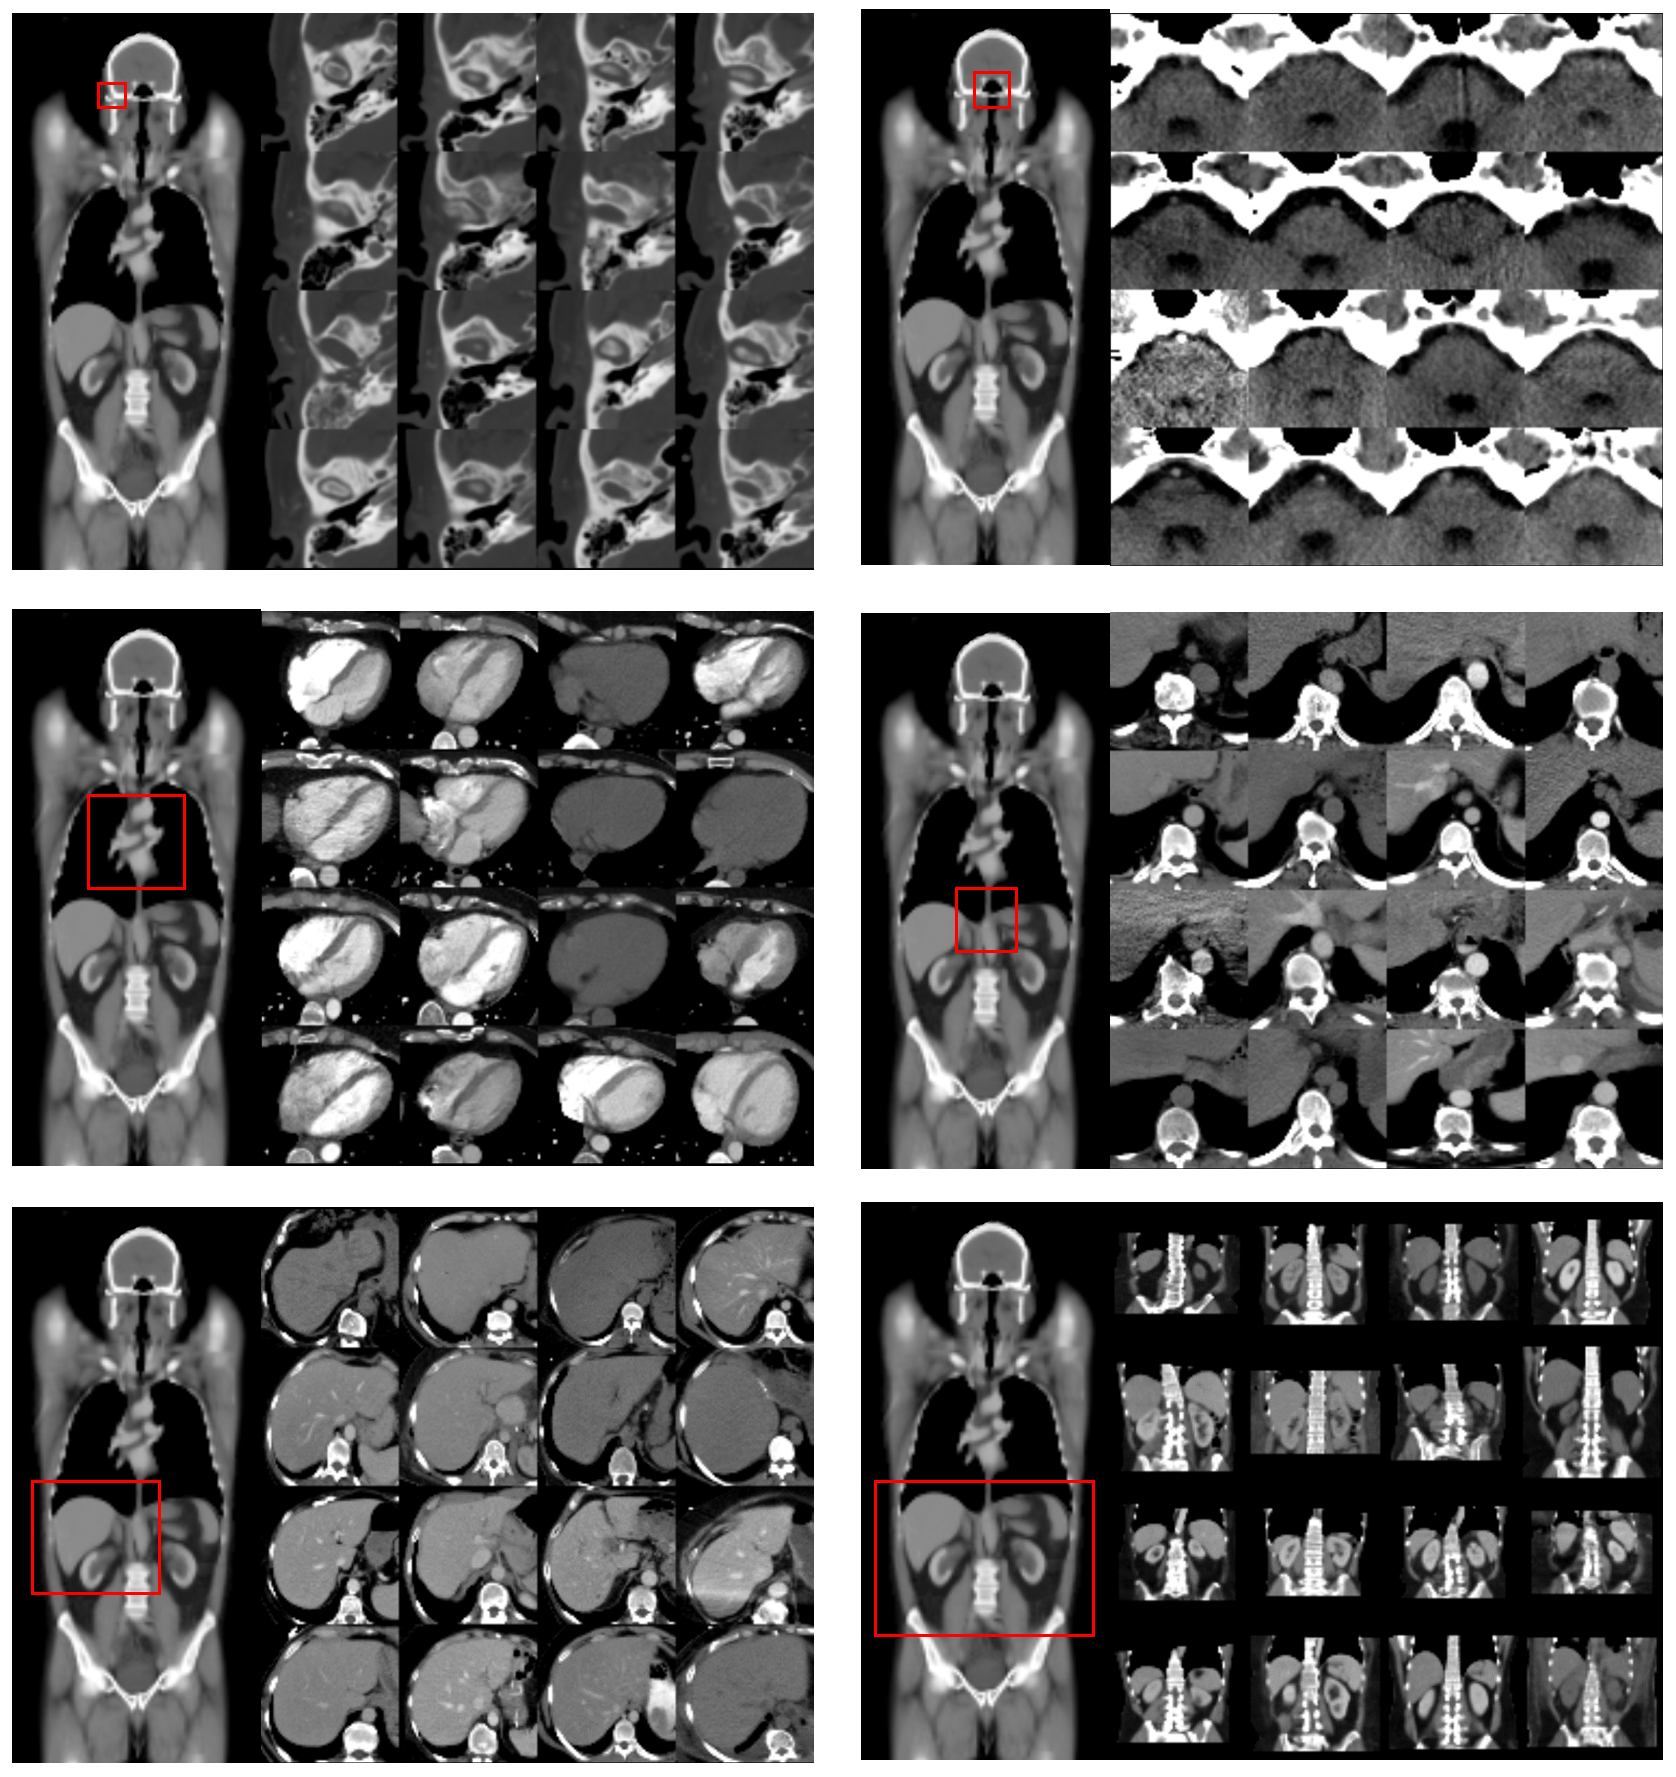

Refer to caption

Figure 6: Overview of Cascaded Strategy. To accommodate high-resolution 3D volumes within GPU constraints, a cascaded modeling strategy utilizes fixed input shapes resampled to progressively higher resolutions. In this example, large field-of-view volumes from the head and neck region are resampled to include only more focused views of the head, and subsequently, the orbit. In each step, DeepATLAS model predictions (converged from the prior round of training) are used to project a template bounding cube representing target anatomy defined in the learned atlas space onto all exams (curved red arrow), which in turn are used to produce the next iteration of higher resolution inputs (straight black arrow).

5.2.4 Cascaded Model

As DeepATLAS model predictions are inherently dependent on broad contextual information, a 3D model is required for robust performance. However, GPU memory constraints as well as heterogeneity in exam resolution preclude direct optimization on raw full-resolution data. As a result, DeepATLAS implements a cascaded modeling strategy with fixed shape 3D inputs resampled to progressively higher resolutions (Figure 6). In the first stage of model training, all original data is resampled to a (64,64,64,1)6464641(64,64,64,1) input and used directly for model training. In the subsequent stages of model training, initial predictions are used generate increasingly higher resolution (64,64,64,1)6464641(64,64,64,1) inputs focused on specific target anatomy used for further model training. In this manner, arbitrary increases in prediction resolution may be achieved despite a relative small 3D input shape.

An overview of the iterative cropping procedure is shown in Figure 6. The key insight is recognizing that the DeepATLAS model itself can be used to project a template bounding cube defined in the learned coordinate space onto any exam (curved red arrow), which in turn can generate resampled data in a standard, uniform field-of-view (straight black arrow). Let BT3subscript𝐵𝑇superscript3B_{T}\in\mathbb{R}^{3} represent all points located within a template bounding cube in the learned coordinate space, and Bn3subscript𝐵𝑛superscript3B_{n}\in\mathbb{R}^{3} represent all points projected from the template into an exam-specific space using DeepATLAS predictions. While the mapping from BTBnsubscript𝐵𝑇subscript𝐵𝑛B_{T}\rightarrow B_{n} is nonlinear, a linear affine transformation matrix A𝐴A can be used to approximate this function such that BTABnsubscript𝐵𝑇𝐴subscript𝐵𝑛B_{T}\cdot A\approx B_{n}. Here, A𝐴A can be derived explicitly using a least-squares solution to the linear matrix equation, which can in turn be used to project the original vertices of BTsubscript𝐵𝑇B_{T}. Note that estimating the linear affine matrix in this manner (across all points within BTsubscript𝐵𝑇B_{T} instead of just the 8 vertices) is robust to potential outlier predictions.

Though maximum theoretical dataset-specific performance can be achieved by carefully generating crops to each individual target anatomic structure, these experiments balance a tradeoff between performance and efficiency by utilizing up to two serial cropping operations for increased resolution. From initial full field-of-view predictions, iteratively higher resolution predictions are generated for up to six large field-of-views (head, face, neck, chest, abdomen, pelvis) and fourteen small field-of-views (orbit, parotid space, submandibular space, lower neck, mediastinum, cervical spine, thoracic spine, thoracolumbar spine, lumbar spine, right upper quadrant, left upper quadrant, right renal fossa, left renal fossa, lower abdomen), if present in the exam.